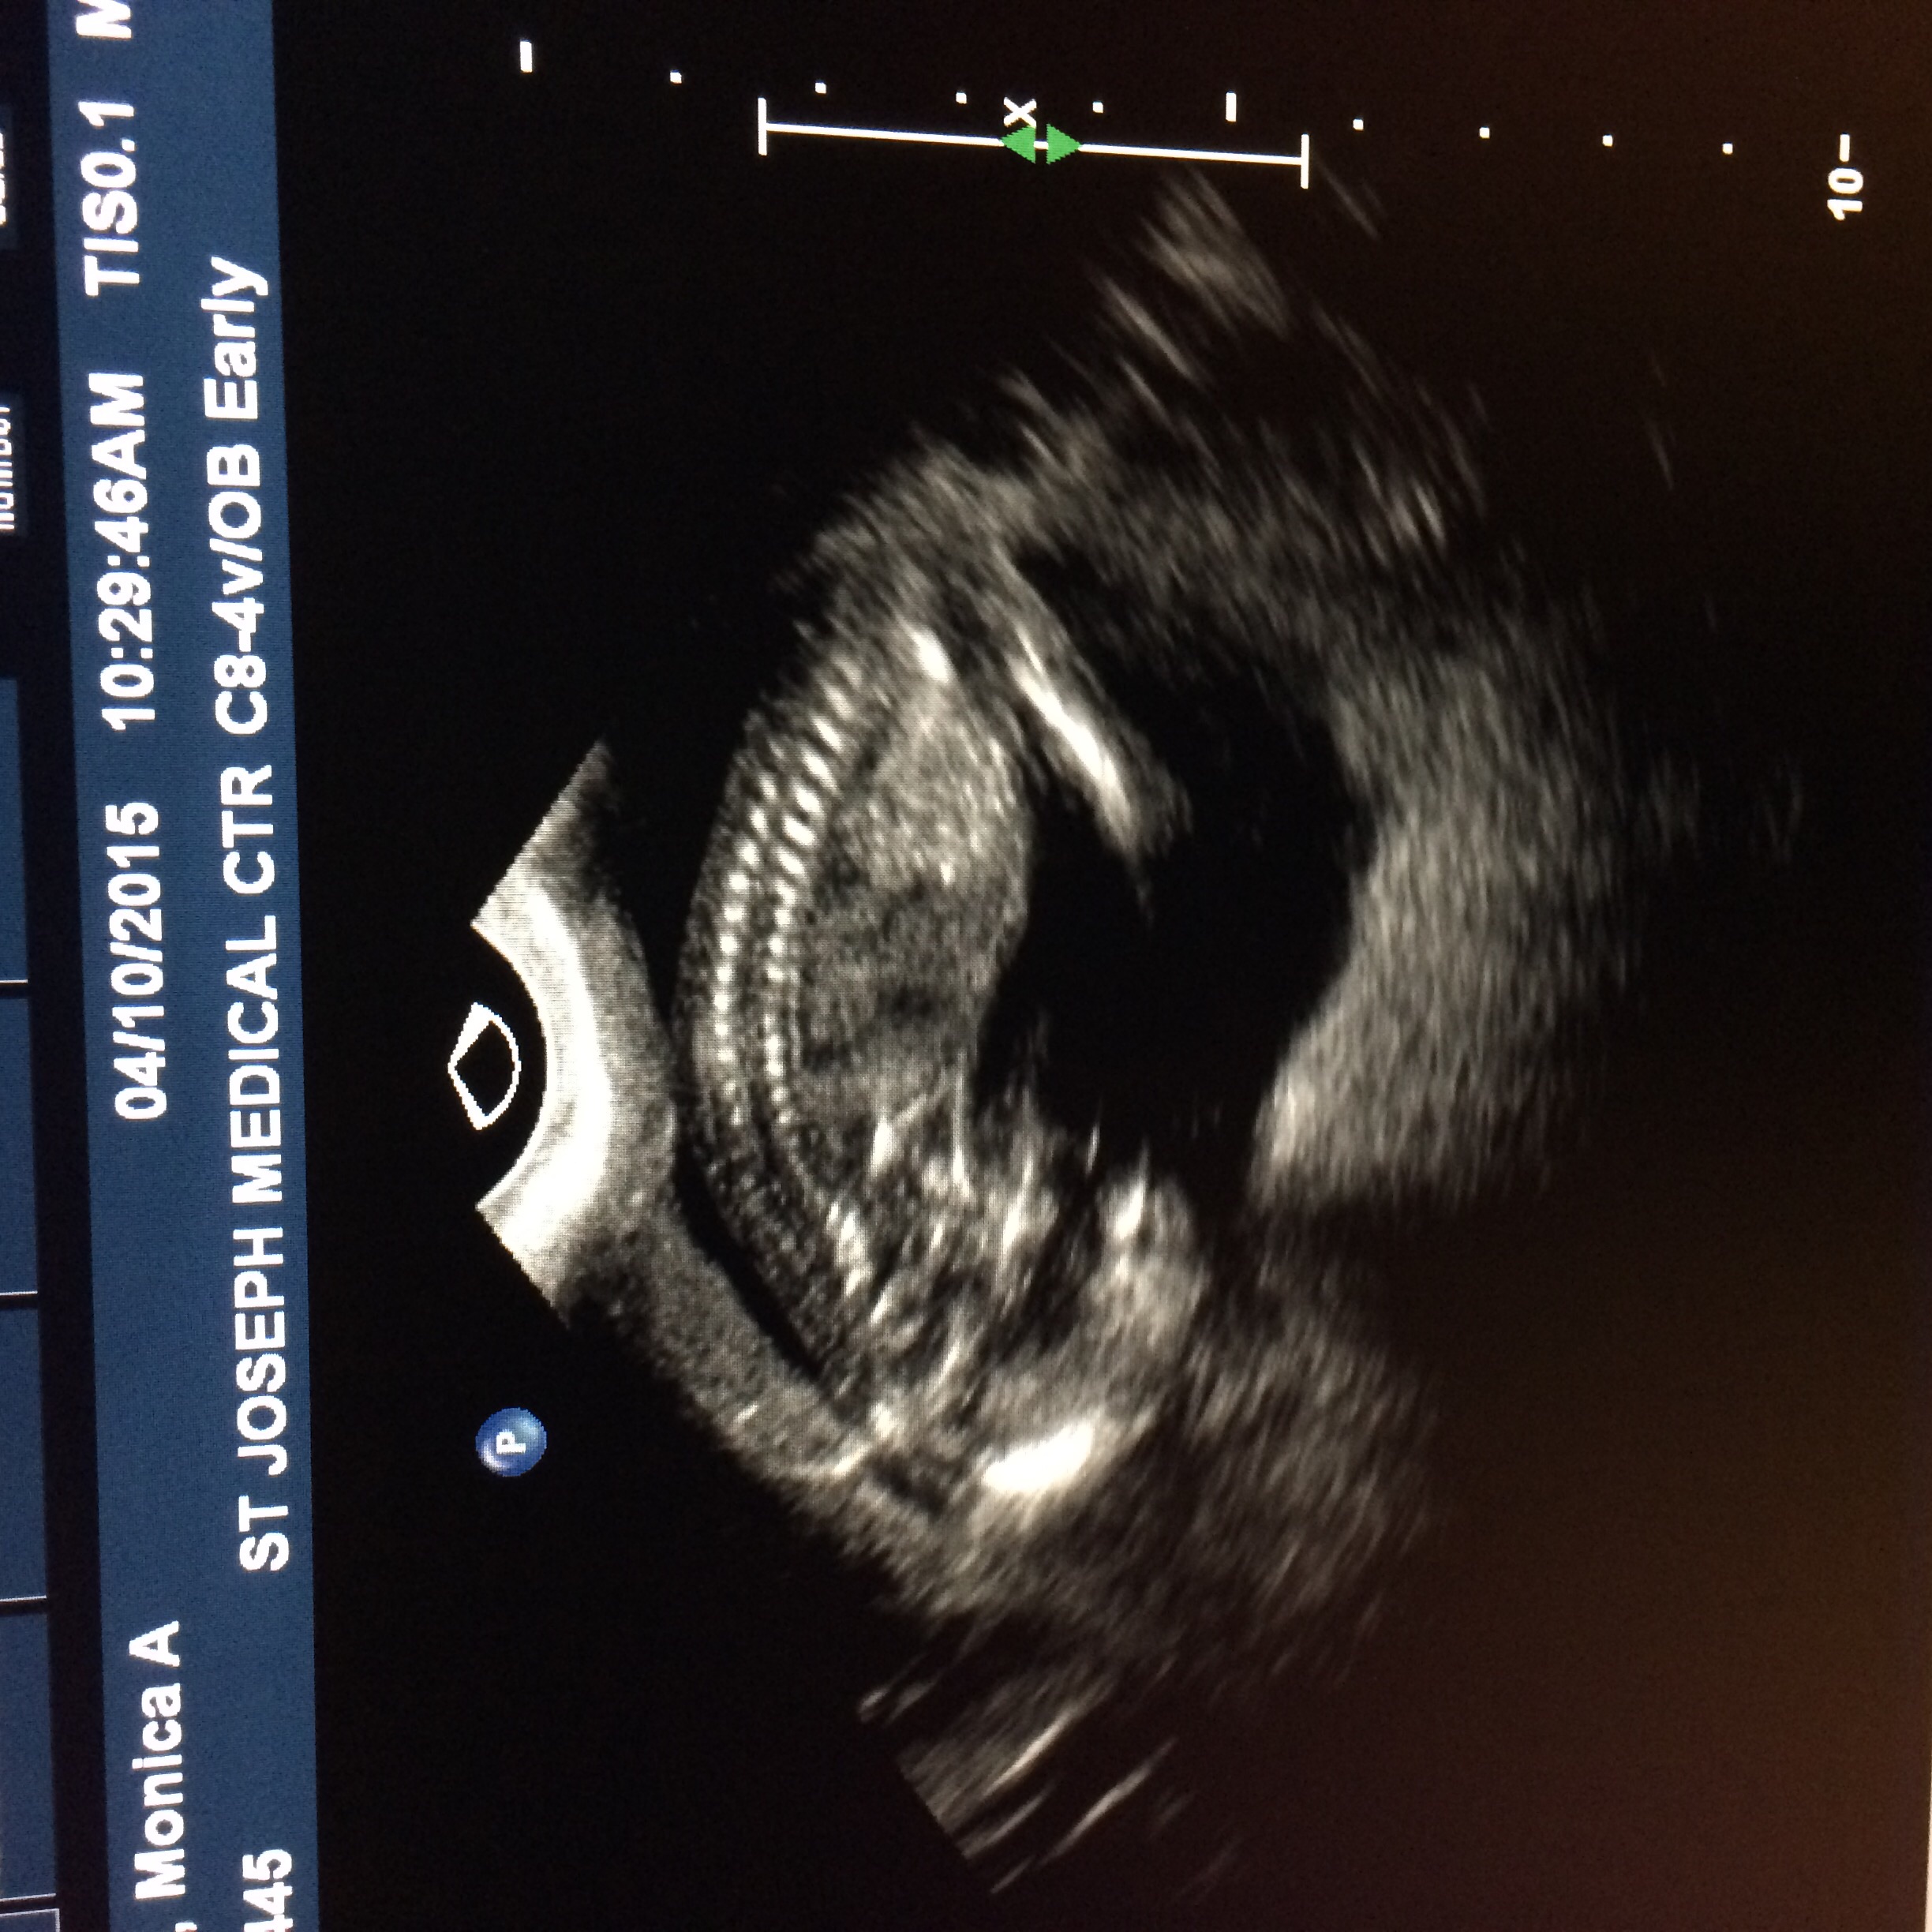

i don't see many topics of any baby's being diagnosed with it.. I don't feel alone but curious if anyone is going through the same and patiently waiting for their little bundle to come into the world to enjoy them either way

... we are due Oct 14 but having him on the 7th via c-section. he kicks and moves daily... more than i remember with my other two. plus I have GD and have it this whole pregnancy